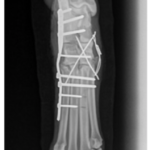

Fractura de radio y cúbito, tratada con una placa y tornillos.